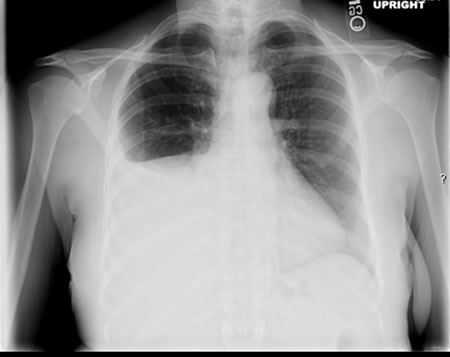

Is almost always abnormal in immunocompetent individuals. Typically presents as fibronodular opacities in upper lobes with or without cavitation. Atypical pattern includes opacities in middle or lower lobes, hilar or paratracheal lymphadenopathy, and/or pleural effusion.[Figure caption and citation for the preceding image starts]: Pulmonary TB with cavitationFrom the personal collection of David Horne and Masahiro Narita; used with permission [Citation ends].